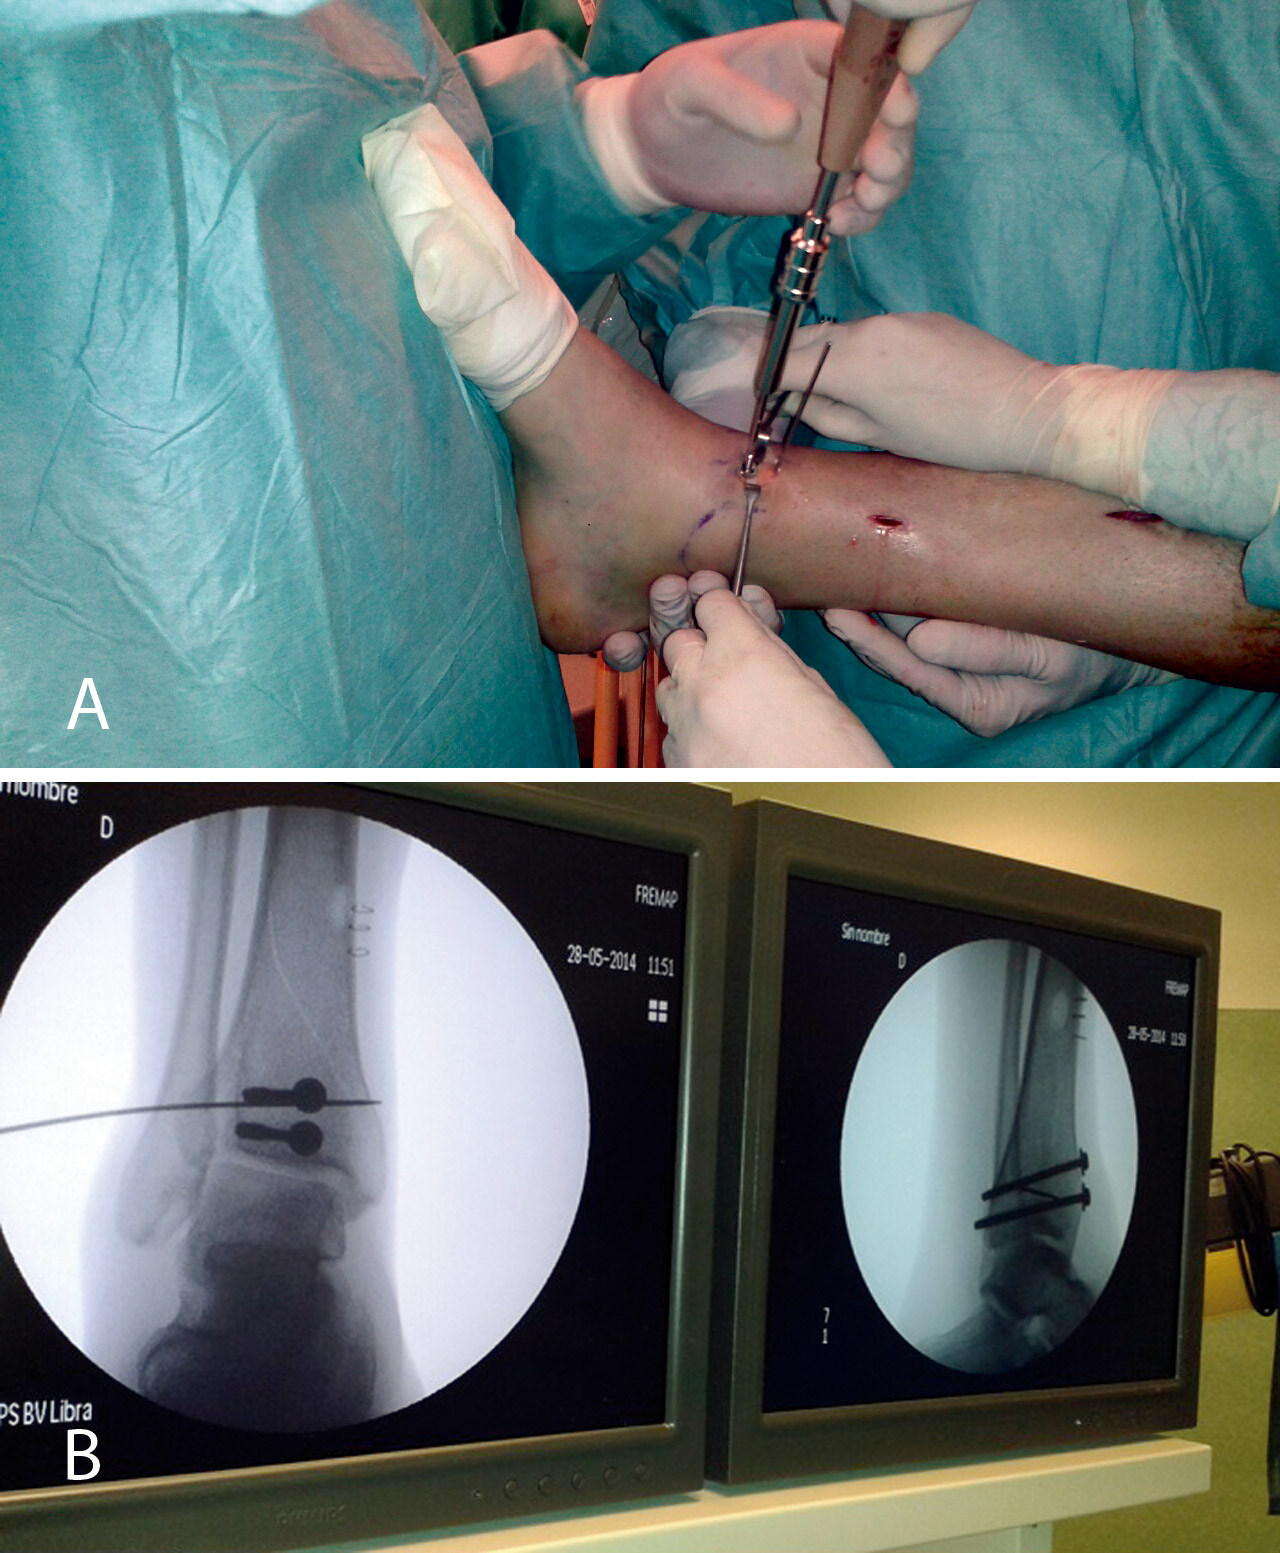

Realizamos los portales artroscópicos habituales en función de la situación de los extremos óseos de la fractura y practicamos un procedimiento idéntico al anterior: lavado, desbridamiento e identificación del foco de fractura (Figuras 12 a 16).

Figura 12. Caso 2: fractura espiroidea con afectación articular. Posicionamiento en férula de Braun. Tracción con vendas. Realización de portales.

Figura 13. Posteriormente, realizamos la limpieza del foco con cucharilla y la reducción del mismo mediante pinzas de cóndilo bajo control radioscópico/artroscópico, y fijación provisional con agujas de Kirschner.

Figura 14. A continuación, se realiza la medición y colocación secuencial de los tornillos.

Figura 15. Por último, se procede a la colocación definitiva de los tornillos.

Figura 16. Resultado final a los 4 meses.

3. Fractura de tipo C: reducción artroscópica, fijación de la epífisis con tornillos canulados y fijación final de la epífisis a la diáfisis por técnica MIPO.

En este caso, es esencial observar las Rx con y sin tracción que nos indican cómo se va a comportar la fractura. Si la fractura es reductible en tracción, es muy probable que podamos realizar una osteosíntesis con restitución completa de la superficie articular. Al realizar la TC, apreciamos la disposición de los fragmentos para marcar una estrategia de reducción bajo control radioscópico y artroscópico, y colocación de los tornillos canulados que fijarán la epífisis distal de la tibia.

Posteriormente, colocaremos la placa en la tibia por vía MIPO realizando una incisión interna, separando la vena safena y deslizando la placa que se fija de manera provisional. Tras comprobar por radioscopia la buena posición del implante, se realiza la fijación definitiva con los tornillos que consideremos adecuados. En el caso de que tengamos que usar un fijador, este sustituye a la placa interna (Figuras 17 a 20).

Figura 17. Caso 3: fractura tipo C. Radiografías sin tracción y con tracción comprobando la reducción.

Figura 19. Colocación del tornillo en el Tillaux con la extremidad en tracción y posteriormente la placa MIPO (minimally invasive plate osteosynthesis).

Figura 20. Radiografías postoperatorias y resultado final con movilidad completa en flexoextensión del tobillo.